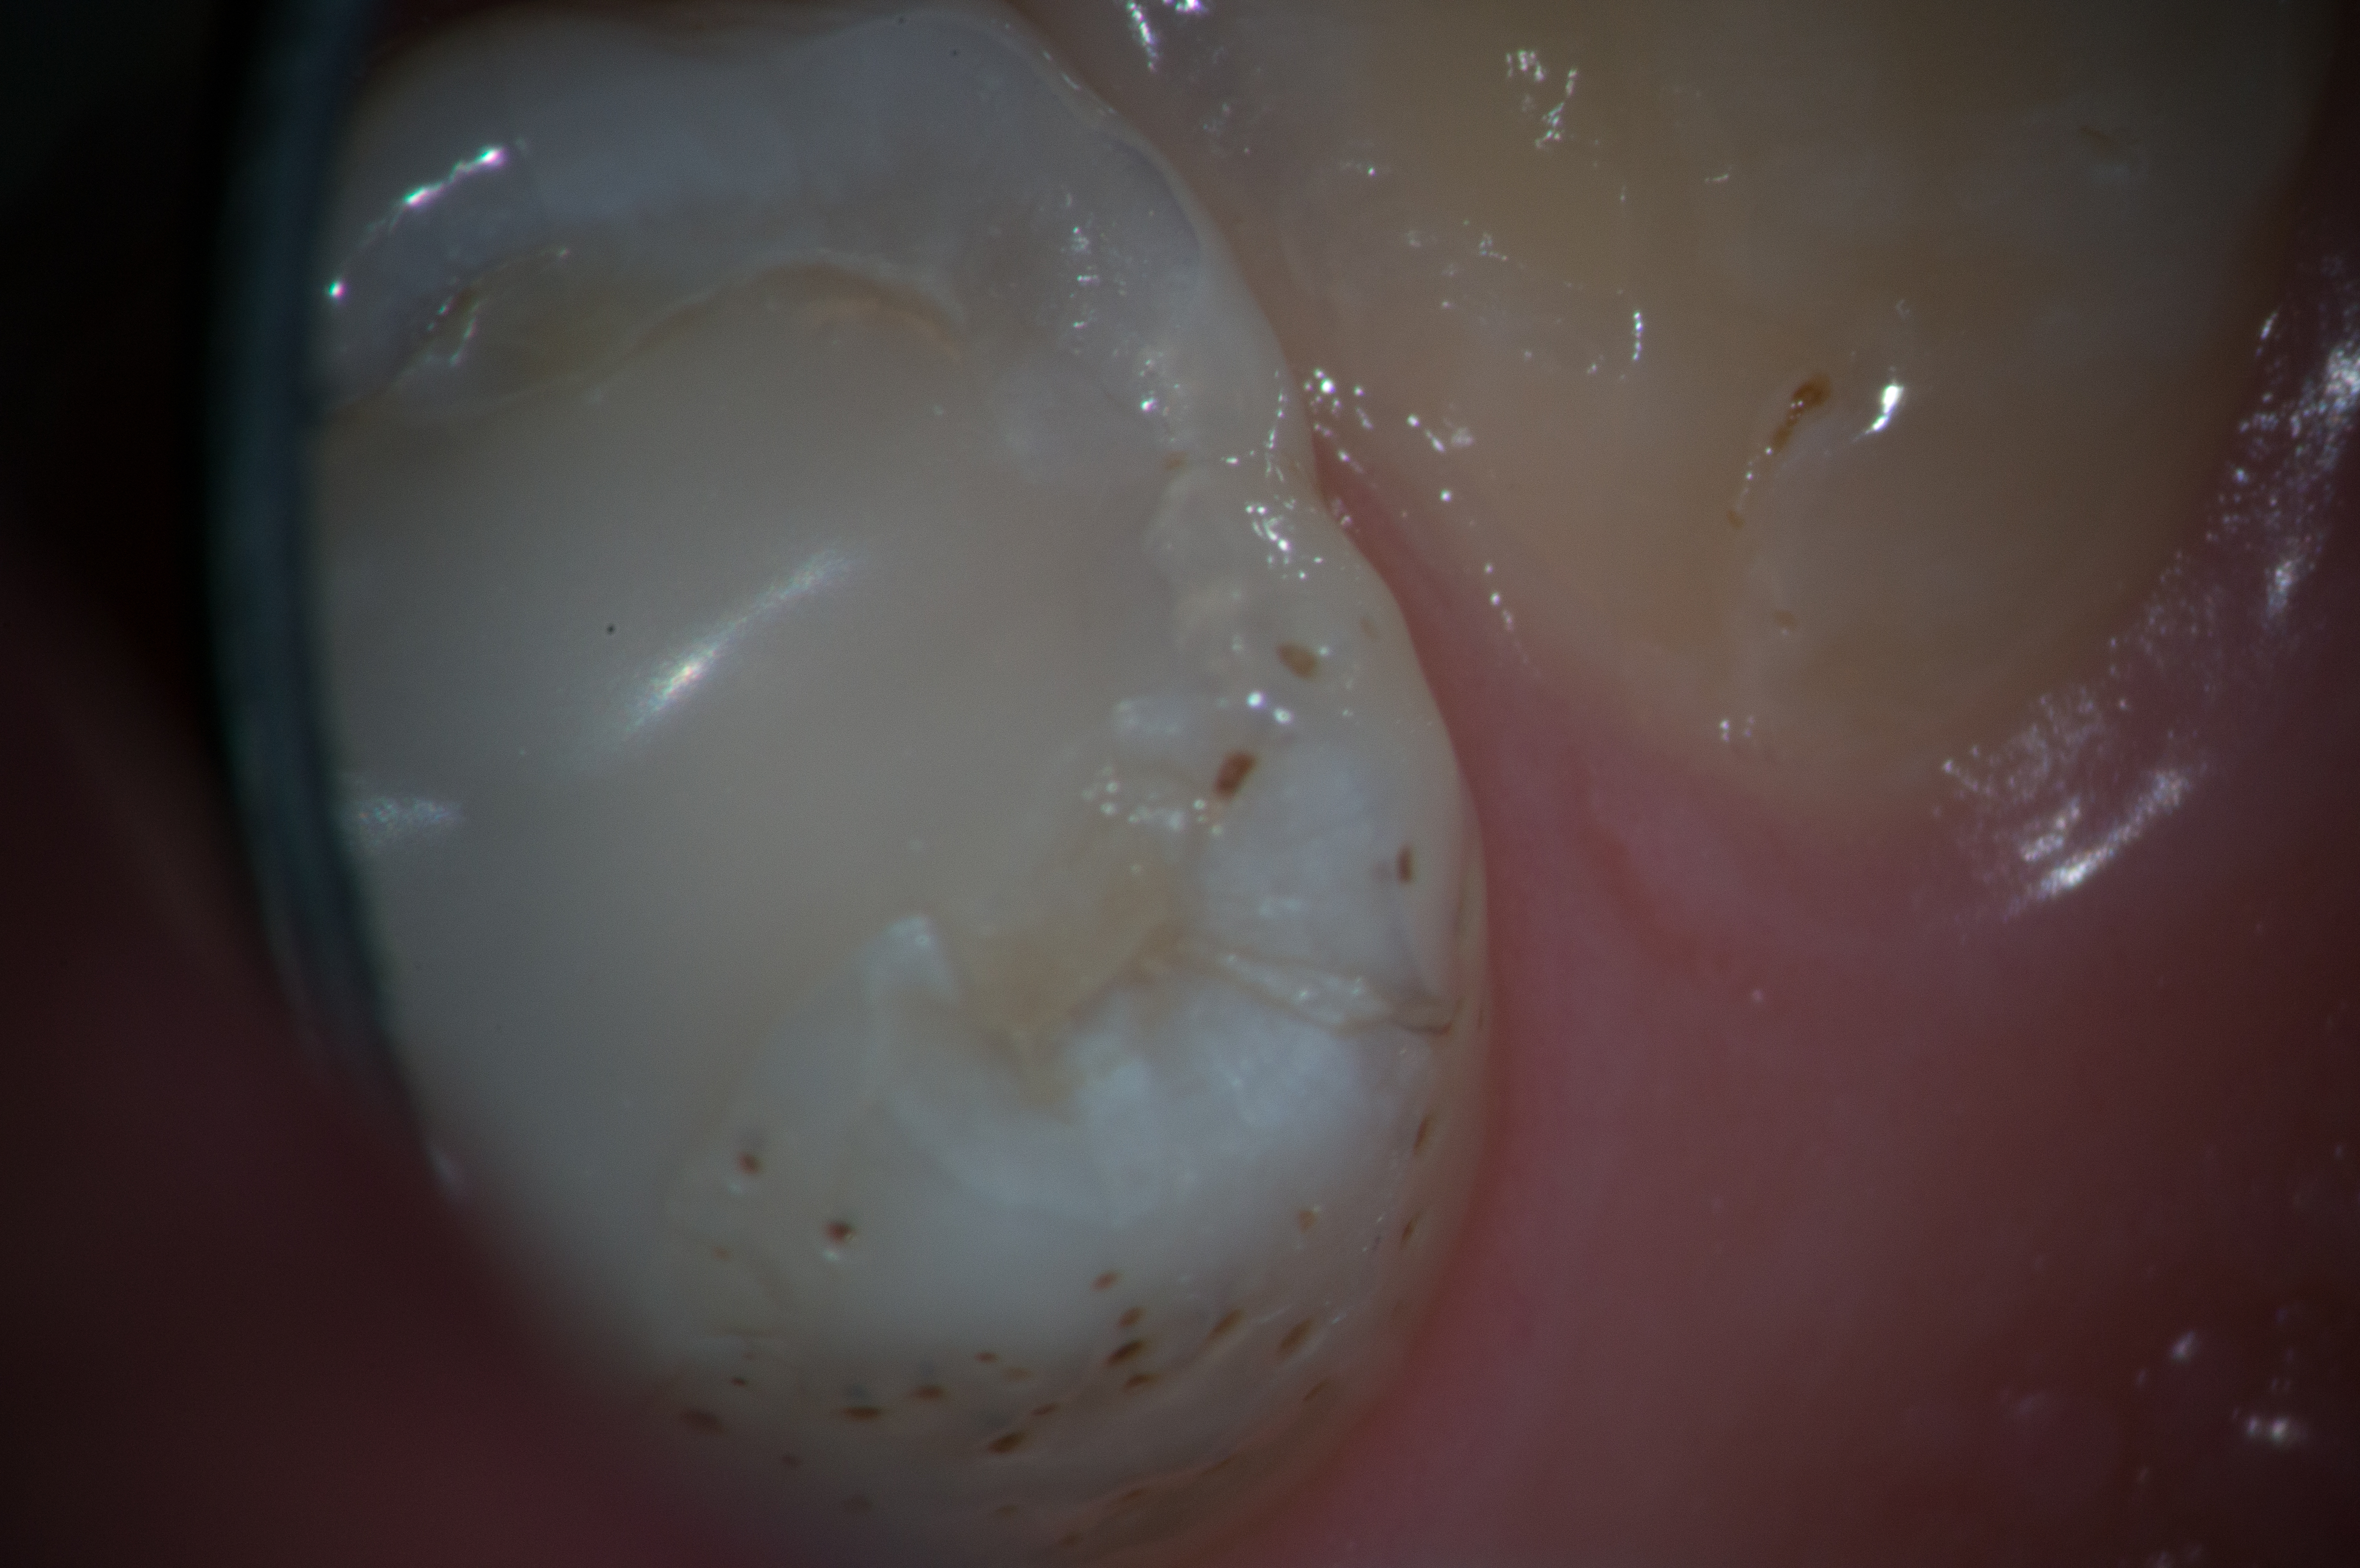

Kaps Fototubus für Sony NEX